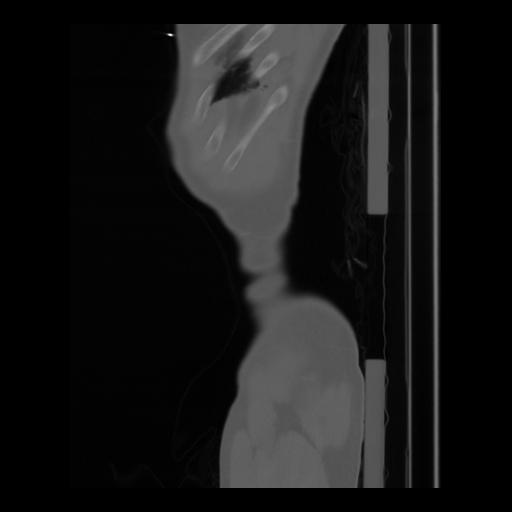

36 CUERPO,CE,Sagittal,3.000,CUERPO,Sagittal,